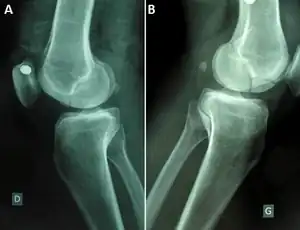

| Segond fracture | Paul Segond | lateral tibial plateau avulsion fracture with anterior cruciate ligament tear | Segond fracture at Who Named It? | ||